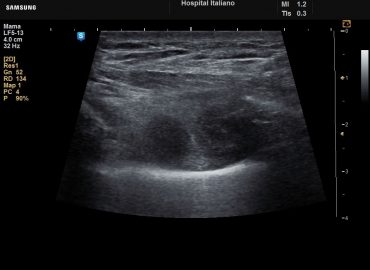

Paciente con masa palpable en mama